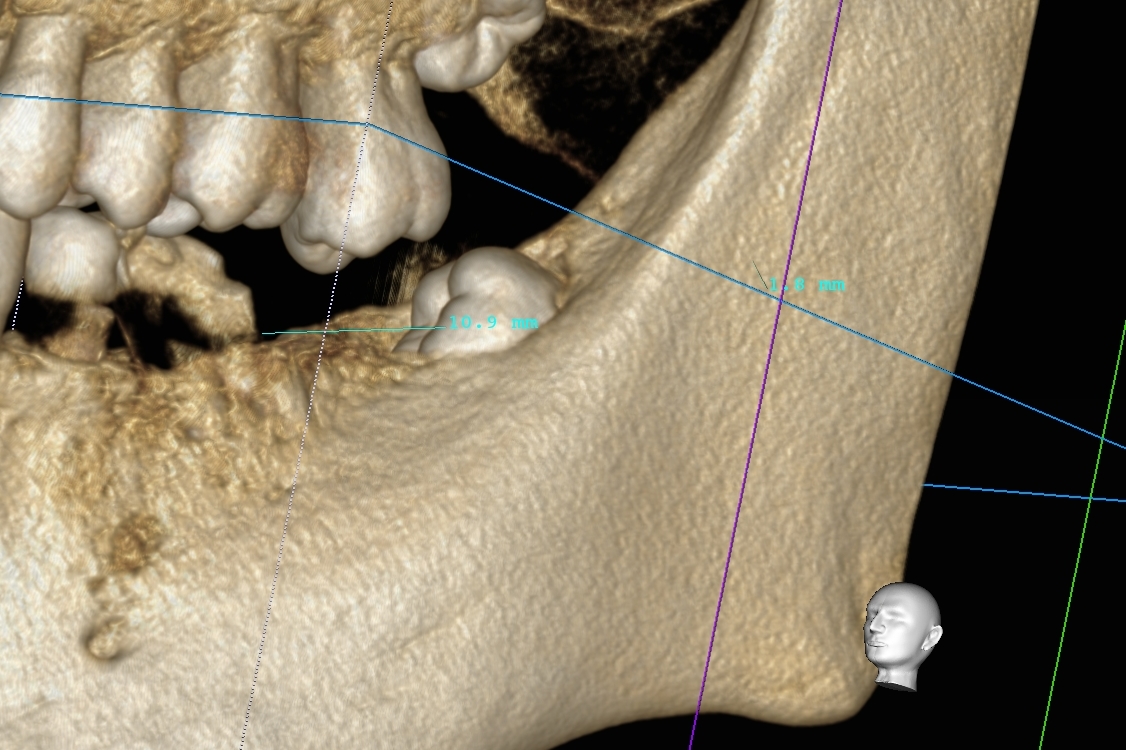

今回はほぼすべてが歯茎の下に埋まった親知らずの抜歯です。

最初、お口に中に親知らずが見えなかったので、手前の歯から化膿したのかと思いましたが、原因はこの親知らずでした。

この状態では、どこにどう埋まっているのか不明なためCT撮影を行いました。それが以下の画像です。

どのように歯が生えているのか明確にわかりました(^^)/